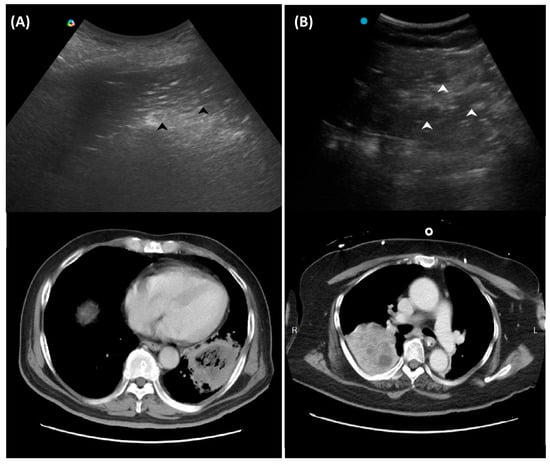

In addition to standardized lateral cephalometric radiographs, comprehensive assessment using dental cone-beam computed tomography (CBCT) and CT has become commonplace in the diagnosis and treatment of jaw deformities. Simulation based on cephalometr...